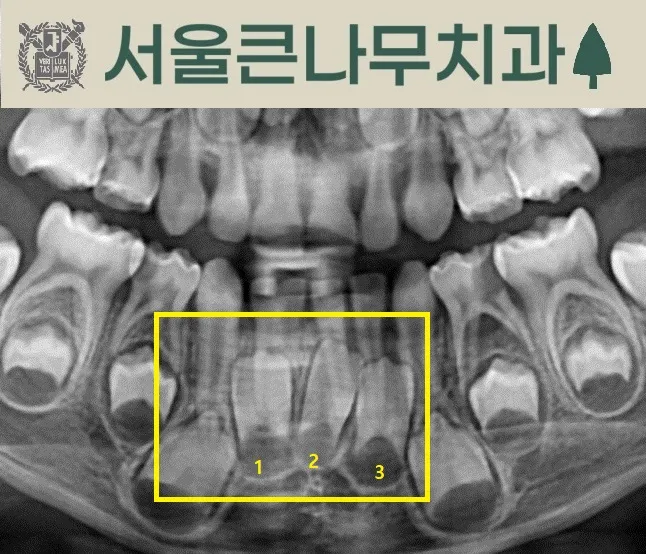

아래 앞니가 쌍생치인 경우입니다.

앞니 영구치가 4개가 아닌 3개인 모습입니다.

이렇게 유치가 쌍생치일 경우 영구치가 선천적으로 결손일 수 있습니다. 영구치가 부족하기 때문에 추후 교정 치료가 필요할 수 있습니다. 되도록이면 빠른 시간 안에 발견하여 문제를 진단하고 해결 방안을 찾는 것이 좋습니다.